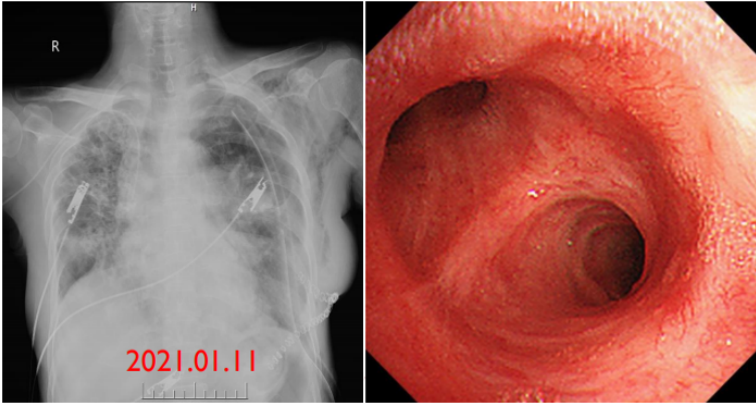

术后第1天:患者无发热,气管镜下示左肺下叶各基底段和背段管腔内少量黄白色黏痰;PCT 0.58 ng/ml(↑),血常规:WBC 12.9×109/L,NEUT% 81.3%,LYM 0.52×109/L。复查胸部CT:左侧移植肺肺野相对清晰,肺外带胸膜下可见少量斑片状磨玻璃(图9)

图片

9  患者左肺移植术后第1天胸部CT(2020-12-31)

术后早期BALF培养提示碳青霉烯类敏感的铜绿假单胞菌,继续哌拉西林他唑巴坦4.5 g q8h ivgtt治疗,加用阿米卡星0.2 g q12h雾化吸入。经治疗,患者无发热、咳嗽、咳痰,可逐步完全脱氧行走。术后第8天,复查胸片示左侧移植肺肺野较前清晰(图10)

10  患者肺移植术后第1天和第8天胸片对比